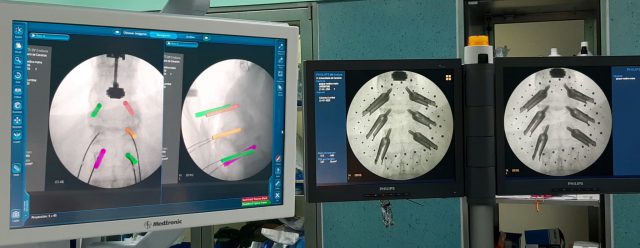

El servicio de Neurocirugía de este centro hospitalario utiliza habitualmente elnavegador en cirugía craneal y ahora ha incorporado esta tecnología en cirugía de columna, lo que permite una precisión milimétrica en la colocación de los implantes, menor tiempo de intervención y disminución en la dosis de radiación intraoperatoria.

Con la ayuda del navegador se consigue la mejoría clínica (menos complicaciones, menor número de recurrencias del proceso, etc.), la disminución del tiempo quirúrgico, que lleva aparejada una menor morbilidad y una menor estancia media. Señalar también la disminución de la carga emocional del cirujano a la hora de enfrentarse a cirugías de revisión complejas.

Destacar también la importancia del navegador como instrumento educacional. La correlación constante entre la localización del instrumento quirúrgico y el lugar del campo operatorio, acelera las curvas de aprendizaje. La utilización de pantallas indica a todos los profesionales que participan en el quirófano de la situación y la etapa en la que se encuentra la cirugía con lo que se sienten más involucrados en el acto quirúrgico.